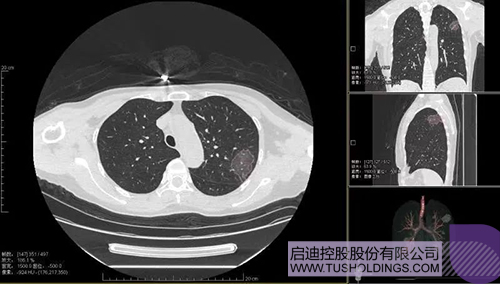

2020Äê2ÔÂ11ÈÕ£¬×¯ÏÐÆåÅÆ¹ÙÍø¹Ù·½°æ¿Æ·þͶ×ÊÆóÒµ¡ªÉñÖݵÂÐÅÍÆ³öйڷÎÑ×¼ì²â¼°Á¿»¯ÖÇÄÜÆÊÎöϵͳ£¬»ý¼«ÖúÁ¦Ò»ÏßÒ½ÎñÈËÔ±¿ÆÑ§¾«×¼·ÀÒß¡£

2020Äê3ÔÂ4ÈÕ£¬¼ÌÓÉׯÏÐÆåÅÆ¹ÙÍø¹Ù·½°æÖ®ÐǺÍׯÏÐÆåÅÆ¹ÙÍø¹Ù·½°æÔ£÷ë¼ÓÈëͶ×ʵIJúѧÑÐÒ»Ì廯ÏîÄ¿±»¡¶ÐÂÎÅÁª²¥¡·±¨µÀºó£¬ÓÉׯÏÐÆåÅÆ¹ÙÍø¹Ù·½°æ¿Æ·þͶ×ÊÆóÒµÓëÎ÷°²½»´óÁªºÏÑз¢µÄйڷÎÑ×AIÊý×ÖÕï¶Ï¼¼ÊõÒà±»¡¶ÐÂÎÅÁª²¥¡·±¨µÀ¡£